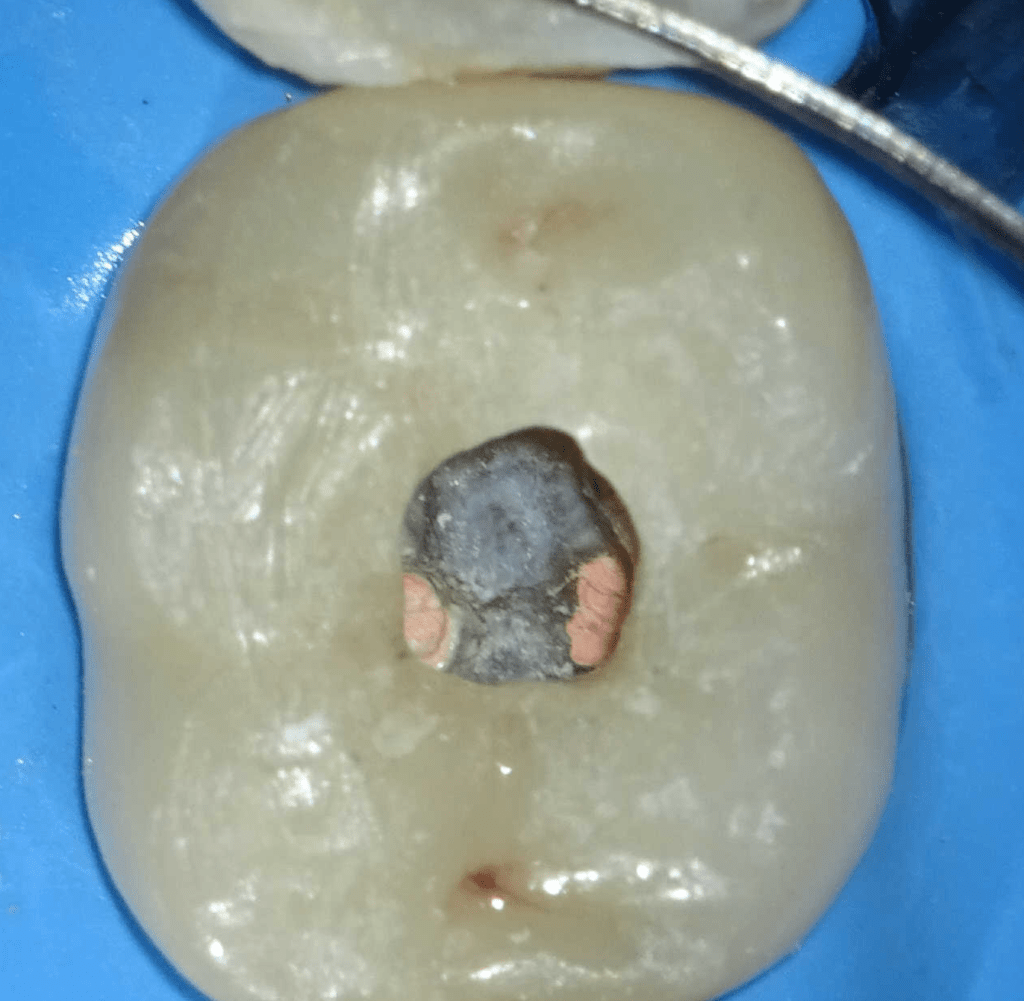

Fisura, remoción amalgama para explorar